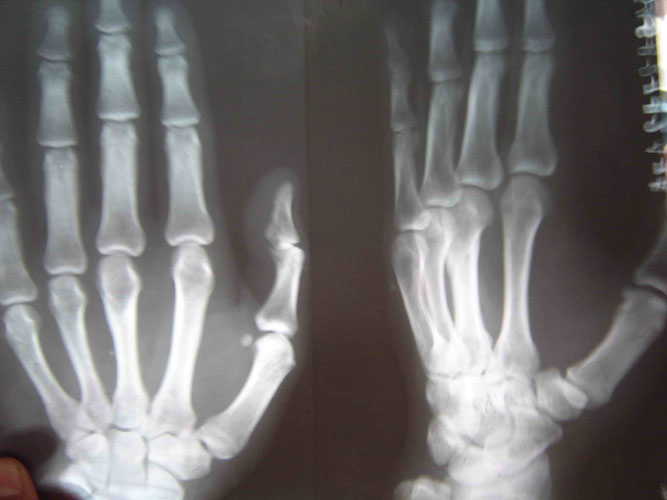

因为剧痛,邢加秋挣脱用手去挡,抬起的手却被犯人李素安抡了一棒,邢眼前一黑晕了过去,不法犯人们又把他打醒,强制他站起来,这时,邢加秋的手背肿得象个馒头,手心青紫,不能动,感觉骨头象断了一样。第二天,犯人李素安、犯人金永军说邢加秋罚站时动摇,对他又一顿毒打,李素安阴险地冲着邢加秋受伤的手砍了一掌,邢大叫一声痛得坐在地上,此后邢家秋的手剧烈疼痛不敢动。(2005年6月在沈阳第一监狱拍的X光片子显示邢加秋左手中指骨折)

这已是两年后的照片了,但仍然清晰可见左手中指骨折的痕迹